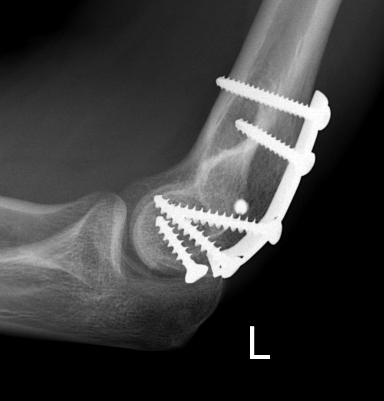

ORIF with PA screws and posterolateral plate

Large capitellum fracture / lateral column ORIF with plate and screws